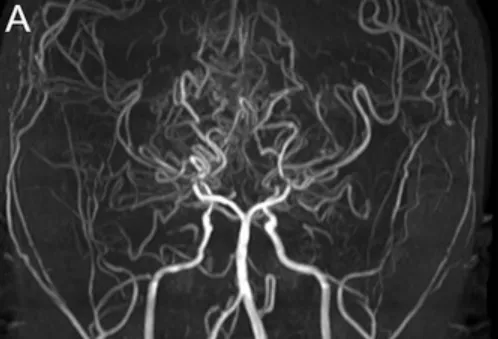

小智首次就诊时,磁共振血管造影(MRA)显示双侧颈内动脉及大脑后动脉狭窄,属烟雾病中晚期(Suzuki 4期)。

MRA与DSA图像清晰显示双侧末端颈内动脉及大脑后动脉狭窄(图A)。